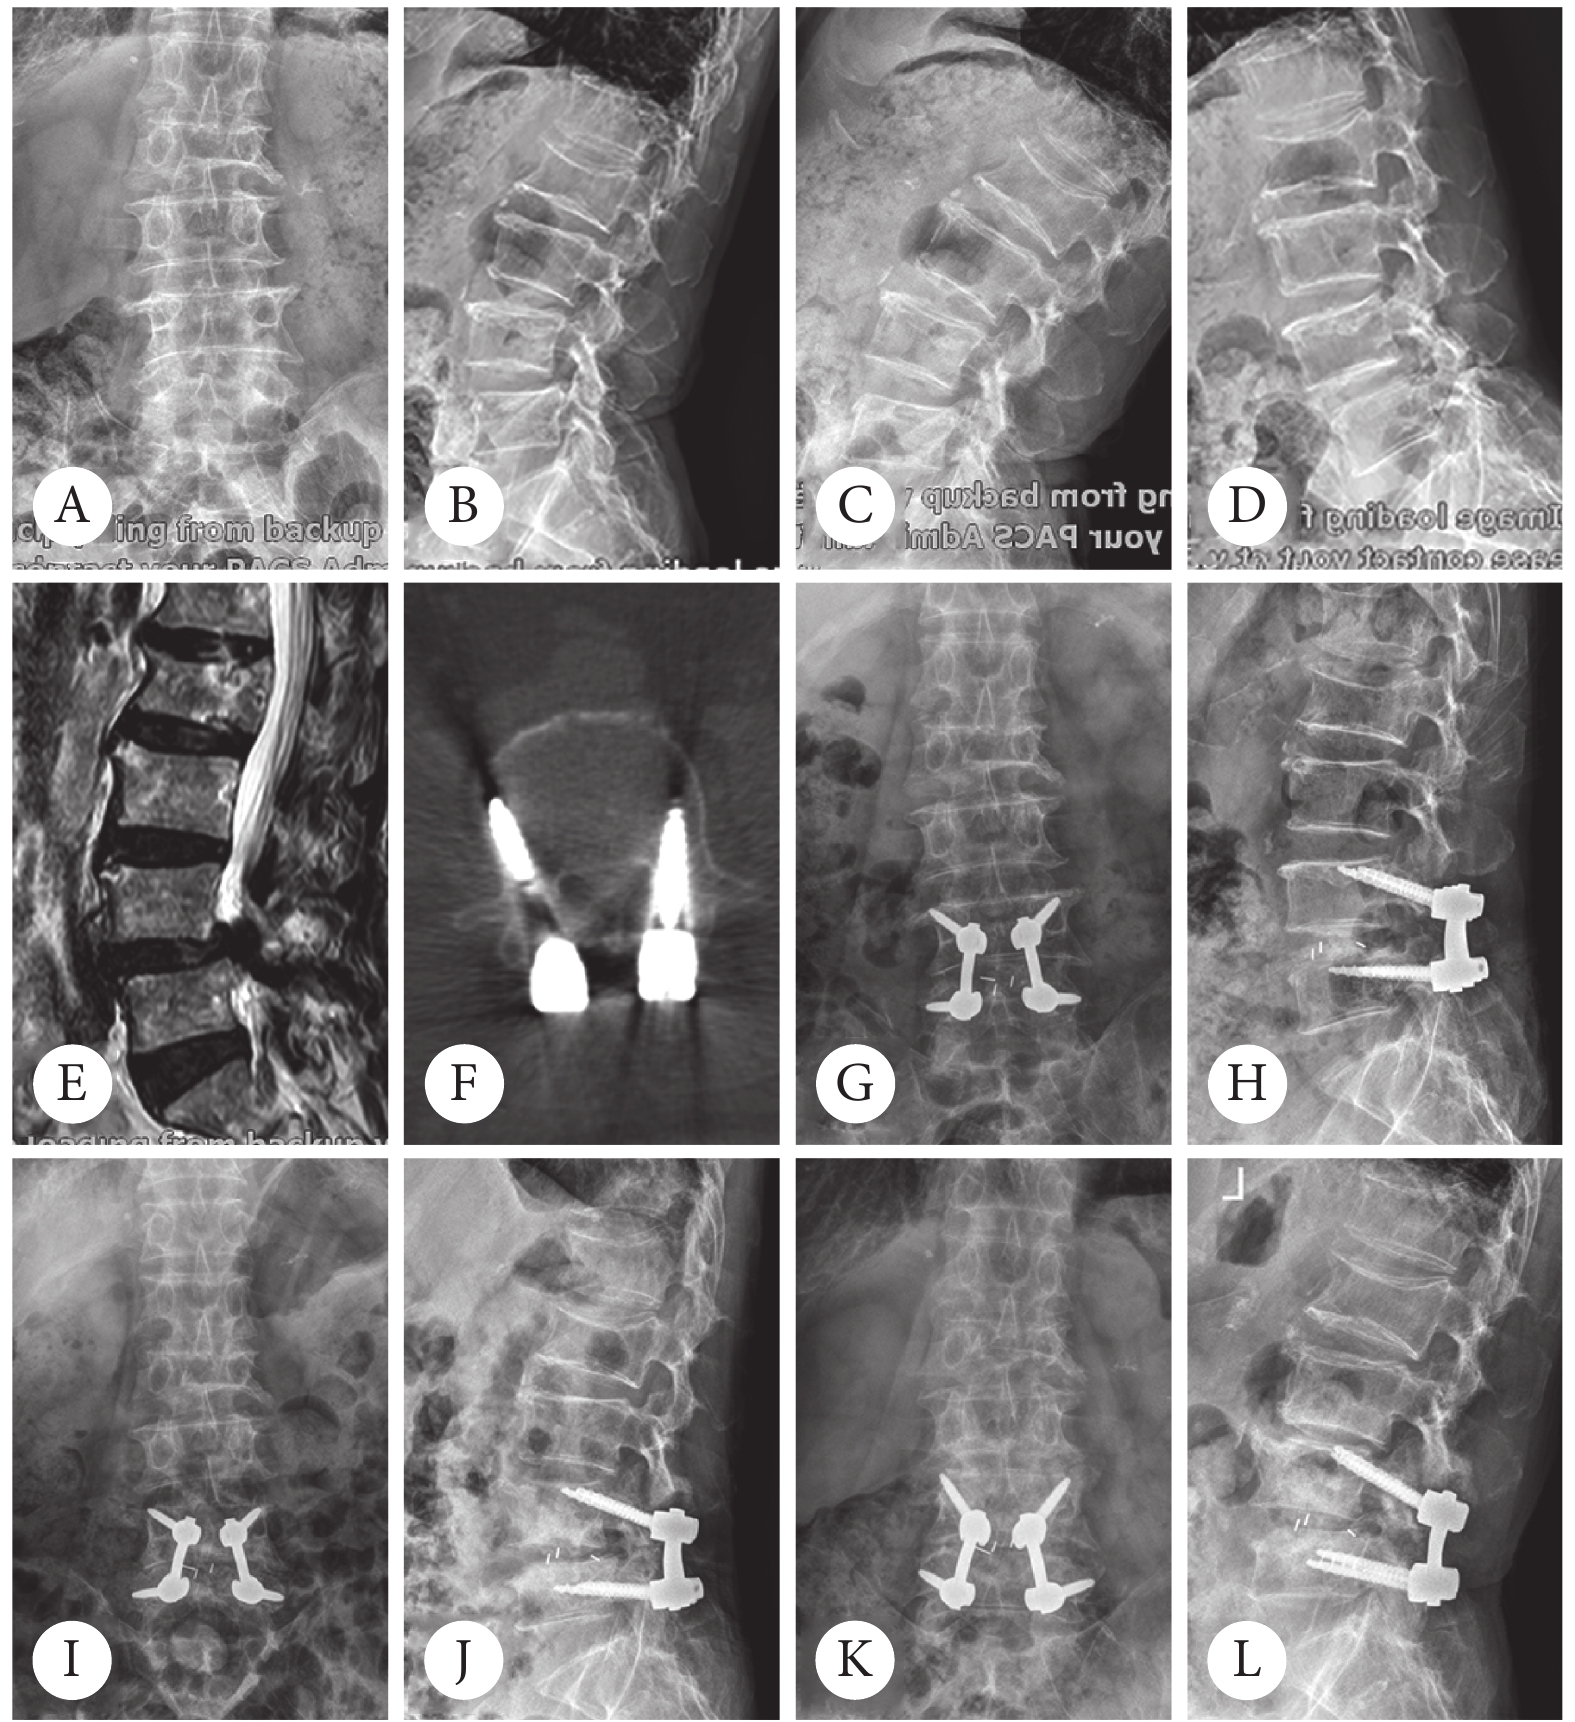

2 临床表现与诊断症状与肿瘤大小及位置密切相关小型肿瘤多无症状,常通过影像学检查偶然发现大型肿瘤可压迫周围组织,导致疼痛肿胀肢体畸形或活动受限,严重时可能压迫神经血管诊断依赖影像学X线CTMRI显示骨内透亮区及钙化灶...